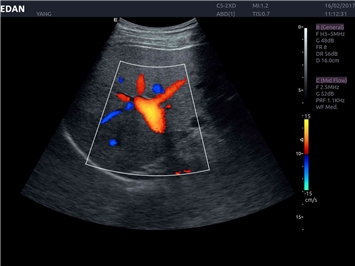

EDAN Acclarix LX4

Расширьте свои представления. Использование усовершенствованной платформой Acclarix система LX4 обеспечивает непревзойденную четкость изображений и интеллектуальный рабочий процесс для всех пользователей, являясь при этом наиболее экономичным решением.

EDAN Acclarix LX4 представляет собой инновационную ультразвуковую систему, построенную на усовершенствованной платформе Acclarix. Сочетание высокого качества визуализации с интеллектуальным рабочим процессом делает эту систему оптимальным выбором для клиник, ценящих эффективность и экономичность.

Области применения:

Система Acclarix LX4 оптимально подходит для:

• Общей визуализации

• Акушерства и гинекологии

• Кардиологических исследований

• Сосудистой диагностики

• Педиатрии

• Исследования малых органов